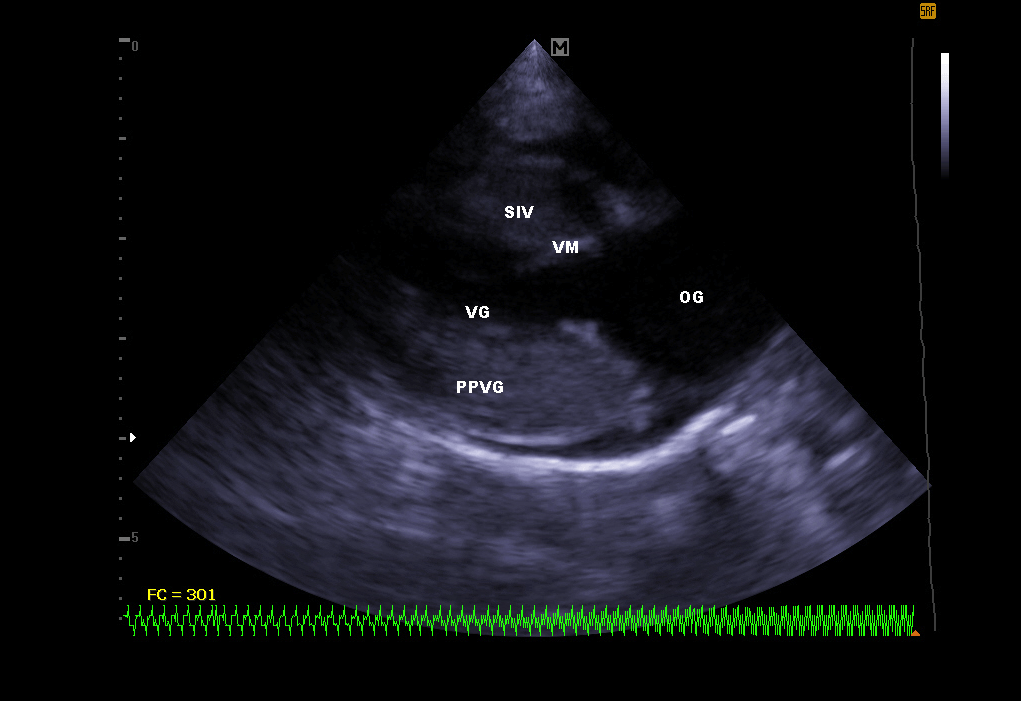

Échographie cardiaque:

Elle permet de visualiser les différentes parties du cœur (parois, cavités, valvules) et de repérer d’éventuelles anomalies qui empêchent un fonctionnement cardiaque correct . En cas d’insuffisance cardiaque, l’échocardiographie permet aussi un suivi régulier de la morphologie cardiaque. Il est alors plus facile de réajuster le traitement mis en place.